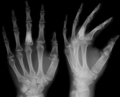

Enchondromas localized in the upper part of the humerus of the same patient

On radiographs, streaks of low density are seen projecting through the diaphyses into the epiphyses of the long bones, due to ectopic cartilage deposits. With age, the cartilage may calcify in the typical "snowflake" pattern.